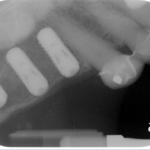

The bone used in a sinus lift may come from your own body (autogenous bone), from a cadaver (allogeneic bone) or from cow bone (xenograft). You will need X-rays taken before your sinus lift so the dentist can study the anatomy of your jaw and sinus. You also may need a special type of computed tomography (CBCT) scan. This scan will allow the dentist to accurately measure the height and width of your existing bone and to evaluate the health of your sinus.